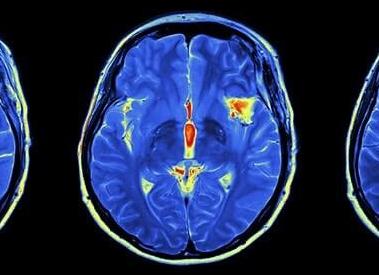

Магнитно-резонансная томография – это медицинский метод диагностики внутренних органов, в результате которого получаются трехмерные послойные изображения мозга. В основе МРТ – воздействие магнитного поля на протоны водорода, которые под внешним влиянием способны изменять свою конфигурацию. Эту смену регистрируют датчики томографа. Информация отправляется в компьютер, обрабатывается и выводится на монитор. Врач видит изображение мозга на экране, а пациенту выдаются снимки на цифровом носителе.

Вспомогательный метод для магнитно-резонансной томографии – контрастное МРТ. Контрастное вещество – это препарат, который вводится в сосудистый кровоток. Он обеспечивает более четкую детализацию картины, благодаря чему трудно исследуемые участки мозга становятся доступными. Контрастные вещества обладают парамагнитными свойствами, которые изменяют электромагнитные показатели тканей. Чаще всего МРТ с контрастным усилением используется в диагностике сосудистых нарушений головного мозга.

Результат

В результате диагностических исследований создается трехмерная модель кровотока в обследуемом участке головного мозга. С помощью МРТ с контрастным усилением также можно получить детальную проекцию сосудов головного мозга и прилегающих к ним тканей. Благодаря этому можно получить точную информацию, которая потребуется для постановки точного диагноза и выбор правильного лечения.

Основное назначение МРТ с контрастированием – это выявление новообразований и установление их типа (доброкачественная или злокачественная опухоль). Они отчетливо выделяются на общем фоне снимков головного мозга благодаря накоплению в них контрастного вещества. На томографах, поддерживающих свервысокопольный режим, можно диагностировать наличие опухолей от 1 мм в диаметре.